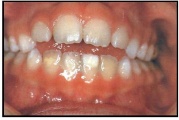

Valehambumus

Hammaste asendianomaaliad on tingitud tavaliselt arenguhäirest.

Sümptomid:

probleemid kõnega

probleemid neelamisega

suuhingamine